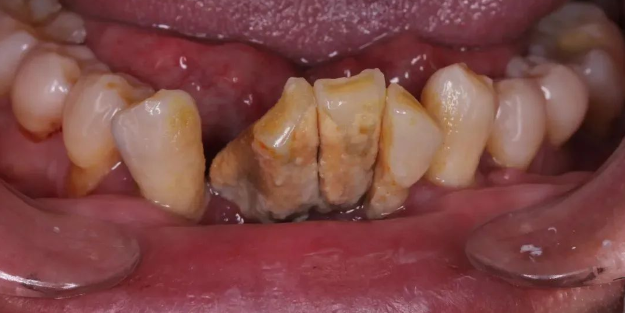

大量牙结石,导致牙齿松动移位,图源:作者提供